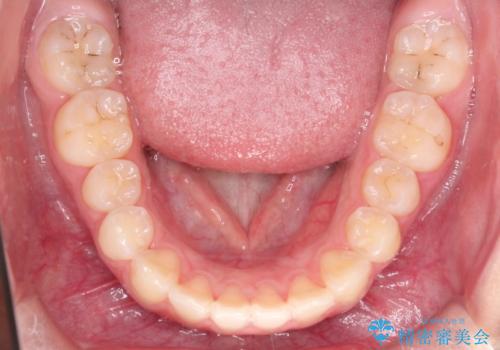

- 前歯が出ているのを主訴に来院されました。

上の前歯が前方に傾斜しており、上の前歯と下の前歯が接触していない状態でした。

上の奥歯を後方に移動させて、前歯を引っ込める計画としました。

しっかり使っていただけたので、スムーズに治療を終了することができました。